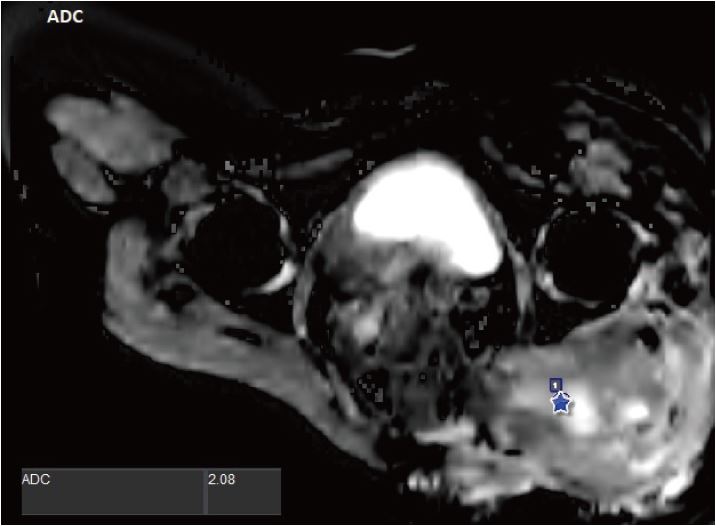

Розрахунок дифузії та ADC (рис. 4) також є придатними інструментами для диференціації міксоїдних пухлин від іншого типу саркоми з досить високими значеннями (2,08 +/- 0,51,10-3 мм2/с) відносно високої частки муцину та низький вміст колагену.

Рисунок 4